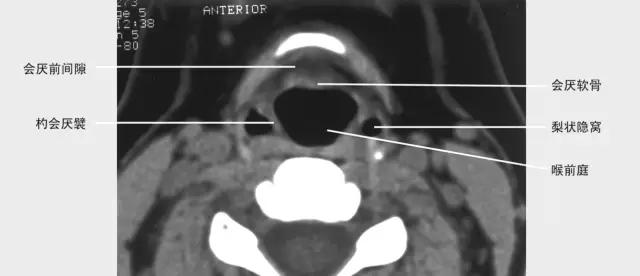

正常喉部CT